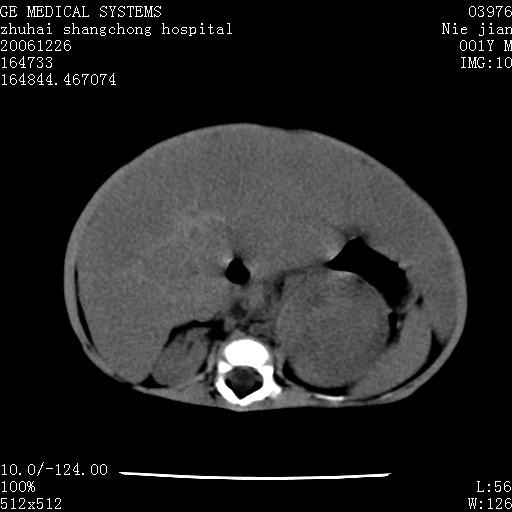

3个月婴儿腹胀来看。

【临床特点】

婴儿,腹胀,无特殊症状,未提供详细资料。

【影像特征】

1、肝明显增大,肝弥漫性低密度灶。

2、肾上腺区见类圆形肿块,其内密度不均,见片状偏高密度。

【诊断】

1、肝弥漫性病变,考虑急性肝炎致广泛脂肪浸润可能性大。

2、肾上腺区占位,假性肿瘤?肾上腺血肿(感染所致)?

一年后

1、肝硬化,脂肪浸润消失。

2、假性肿瘤消失或血肿吸收。

【分析】

1、关键着眼点:肝脏弥漫性病变内有没有走形的血管,仔细看部分低密度内有血管影(要有增强扫描作为证据就好了),说明并非肿瘤样病变,而是脂肪浸润。即可能不是转移瘤或原发肿瘤,低密度的形态上看,是片状,也不像肿瘤。

2、儿童肝炎最常见的是感染,有时食入性损害或药物也可致肝脏炎症,肝炎致大空泡型脂肪变性,是一种无痛性疾病,无症状,病因有营养异常、代谢性疾病、药物及病毒感染。所以脂肪变性与感染有关。

3、肝炎的结局是肝硬化,而恰恰一年后复查,已有肝硬化表现。肿瘤一般那会消失,那叫奇迹。

4、肾上腺出血也可见于败血症及感染,通常包块在数周内消失,ct表现包块内有偏高密度,可能是亚急性血肿的表现。假性肿瘤即腹部肠管积液、扩张血管及邻近结构的伪像。自然会消失。

5、因此,感染可以贯穿一切,解释一切。肿瘤自然消退?可能吗?那些应要无道理的创造奇迹的事情会那么容易发生吗?